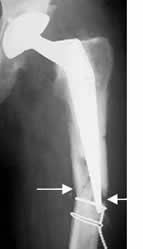

Fig 116. Fractura del material.

Rx AP. Extensa placa de compresión en el fémur. Está rota en su parte distal, con pérdida en la alineación de los fragmentos.